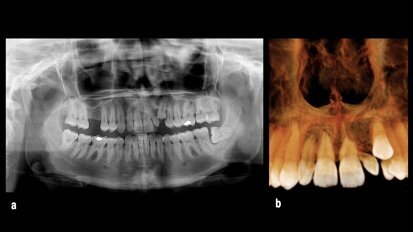

Implantes zigomáticos en el edéntulo maxilar con reabsorción severa

El tratamiento con implantes zigomáticos es una solución viable y predecible para los paciente con reabsorción severa maxilar. Es un método alternativo ...